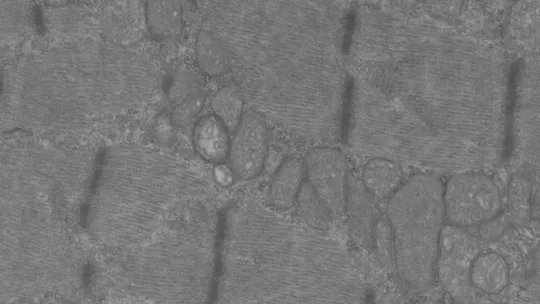

Opa1 is a mitochondrial fusion protein. It serves to fuse the internal membranes of mitochondria. Although present in all cells and tissues (except red blood cells), mitochondria are particularly abundant in muscle and liver, and their main function is to convert the energy in food into energy for cells. Mitochondria are highly dynamic; they join and separate, and grow and shrink constantly. These processes are known as mitochondrial dynamics.

The article describes the animal phenotype and explains that the removal of Opa1 exclusively from skeletal muscle fibre triggers a severe inflammatory process that spreads from the muscle fibre throughout the body. The inflammatory response halts growth and shortens the lifespan of the animal. The scientists also describe the main molecular components of the cell signalling pathway that activates the inflammatory response in muscle.

The head of the study explains that these results are of biomedical relevance. There is a set of diseases known as inflammatory myopathies, of unknown origin, in which patients show chronic muscle inflammation accompanied by muscle weakness. "The results of this study suggest that mitochondrial alterations may underlie inflammatory myopathies. More research is now needed to address this possible link," says the scientist.